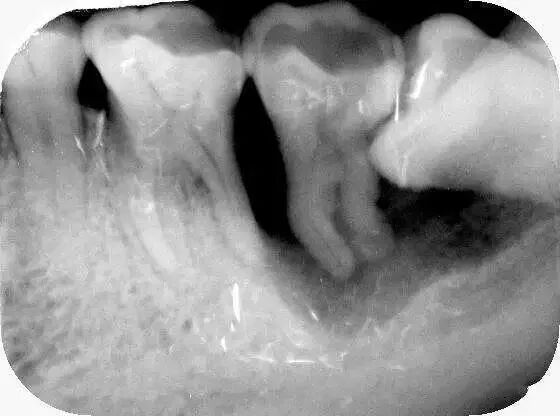

3、邻牙龋坏和牙周炎

智齿与邻牙之间有小的缝隙存在,食物残渣可以留存,长时间就可以导致邻牙发生龋坏和或牙周炎,如图所示: